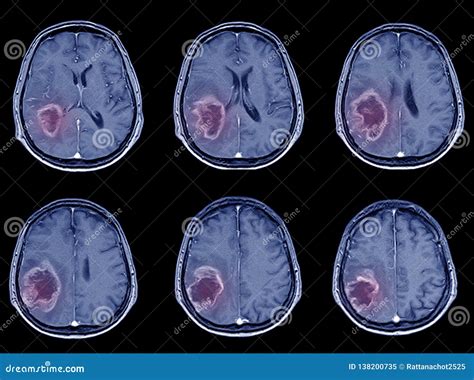

Differentiating Ischemic vs. Hemorrhagic Stroke

One of the main goals of the CT scan is to differentiate between an ischemic stroke and a hemorrhagic stroke. A hemorrhagic stroke involves bleeding in the brain. On a CT scan, blood appears bright white. So, if the scan shows any bright white areas, it’s a sign of bleeding. If there’s no bleeding and the scan looks relatively normal (or shows the signs of ischemic stroke ), then it’s most likely an ischemic stroke . This distinction is super important because the treatments for each type of stroke are different.